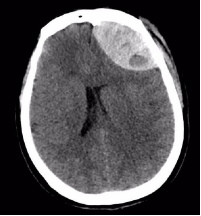

附女士,今年50岁,因车祸头部受伤,意识障碍4小时急诊入院。入院时,患者呈昏迷状,左侧瞳孔散大,头部、腕部、腹部等受伤10余处。急诊CT提示硬膜外血肿,中线移位明显,脑实质明显受压内移,左侧侧脑室受压变窄,病情凶险,手术指征明确。

(术后血肿清除彻底)

术后第一天,患者意识恢复清醒,复查头部CT提示颅内血肿清除彻底。全腹CT、双腕关节CT显示:肠管管壁明显水肿增厚,邻近肠系膜肿胀,肠间隙模糊,盆腔少量积液,腹腔内未见游离积气,提示肠管或肠系膜损伤;右侧月骨脱位,左侧桡骨远端骨折。